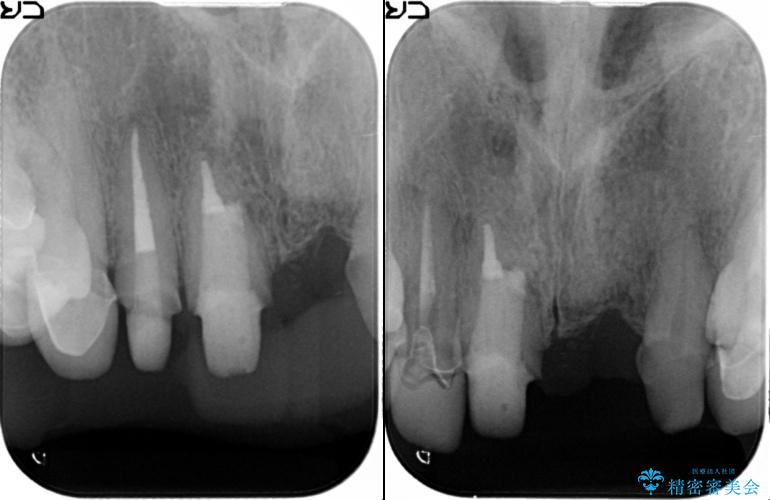

[ セラミック治療 ] 歯ぐきの際の黒ずみを改善したい

- 歯ぐきとセラミックの間の黒ずみが目立つので、きれいに治してほしい。と希望され来院されました。

歯ぐきの位置が変化しクラウン下の歯が見えるようになってしまったことで、審美障害が生じている状態です。

歯ぐきの位置の経年的な変化は、誰にでも起きうる変化です。

強いブラッシングや電動歯ブラシの当て過ぎなども原因の一因となることがあります。